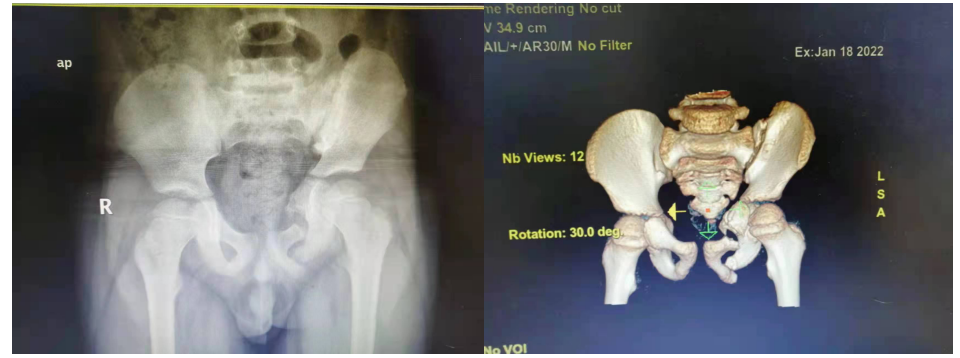

前不久,玉林市中西医结合骨科医院骨盆科住进了一位特殊的小患者,7岁男童甘某。他由于在家玩耍时不慎从3楼(约8米高)跌下,伤后因病情危重,先后辗转三家医院进行抢救治疗,在ICU气管插管治疗1个多月,待病情逐渐稳定后,患儿骨盆骨折却错过了最佳治疗时机。到我院骨盆科治疗时患儿右下肢明显短缩,跛行步态明显。术前的DR及CT检查如下: 术前CT、DT图片

术前,科室治疗团队针对该患儿年纪少,骨盆骨折移位大,按常规成人手术治疗方案手术伤大,失血多,且复位固定困难等特点,具体问题具体分析,计划行截骨矫形内固定+外固定支架外固定手术。术前利用3D打印技术,在3D模型上行置钉及截骨手术模拟操作。李振宏主任带领科室团队,手术内外结合,采用左髂窝加改良stoppa入路,截骨后使用耻骨螺钉加外固定架外固定。手术历时约两个半小时,出血约200毫升,且术中术后未需输血。